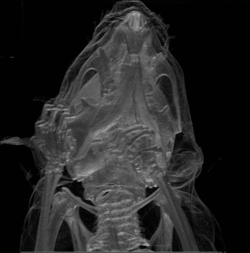

نظرة جانبية لجمجمة إنسان

جمجمة ذكر قوقازي.

جمجمة بشرية (أمامية)

جمجمة بشرية (جانبية)